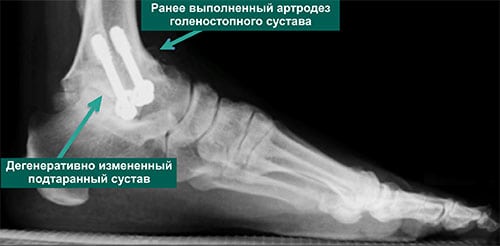

Признаки артроза хорошо визуализируются на рентгенологических снимках. Наблюдается сужение или сращение суставной щели, объединяющей берцовую и таранную кости. Это свидетельствует о значительном поражении всех хрящевых тканей. Методы консервативной терапии тут безрезультативны. Если сохранить сочленение артроскопическими методами лечения (санацией, трансплантацией хрящевых тканей) невозможно, то проводится эндопротезирование голеностопного сустава — его полная замена искусственным протезом.

Самый часто используемый метод хирургического вмешательства при деформирующем артрозе — артродез. Но даже при тщательной реконструкции голеностопного сустава велика вероятность развития серьезных осложнений. Во время операции сочленение дополнительно травмируется, а в реабилитационный период ухудшается трофика околосуставных тканей. Все это ведет к возникновению вторичного остеоартроза. Применение артродезирования становится причиной функциональной несостоятельности стопы, утраты ее компенсаторных функций. Развивается постхирургический остеоартроз, поражающий практически все сочленения стопы. Для него характерны контрактуры, интенсивный болевой синдром. Перераспределяются нагрузки на тазобедренные, коленные, подтаранные, плюсневые суставы, что со временем провоцирует стрессовый деформирующий артроз. Возникает необходимость артродезирования и этих поврежденных суставов.